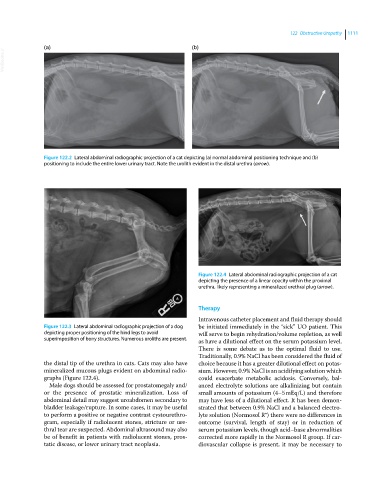

Figure 122.4 Lateral abdominal radiographic projection of a cat

depicting the presence of a linear opacity within the proximal

urethra, likely representing a mineralized urethral plug (arrow).